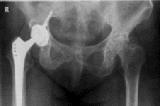

Կոկսարթրոզը կամ կոնքազդրի հոդի ձևախախտված արթրոզը հոդերի ամենատարածված պաթոլոգիաներից մեկն է: Այն ուղեկցվում է հոդի կառուցվածքի և ֆունկցիայի խանգարմամբ...